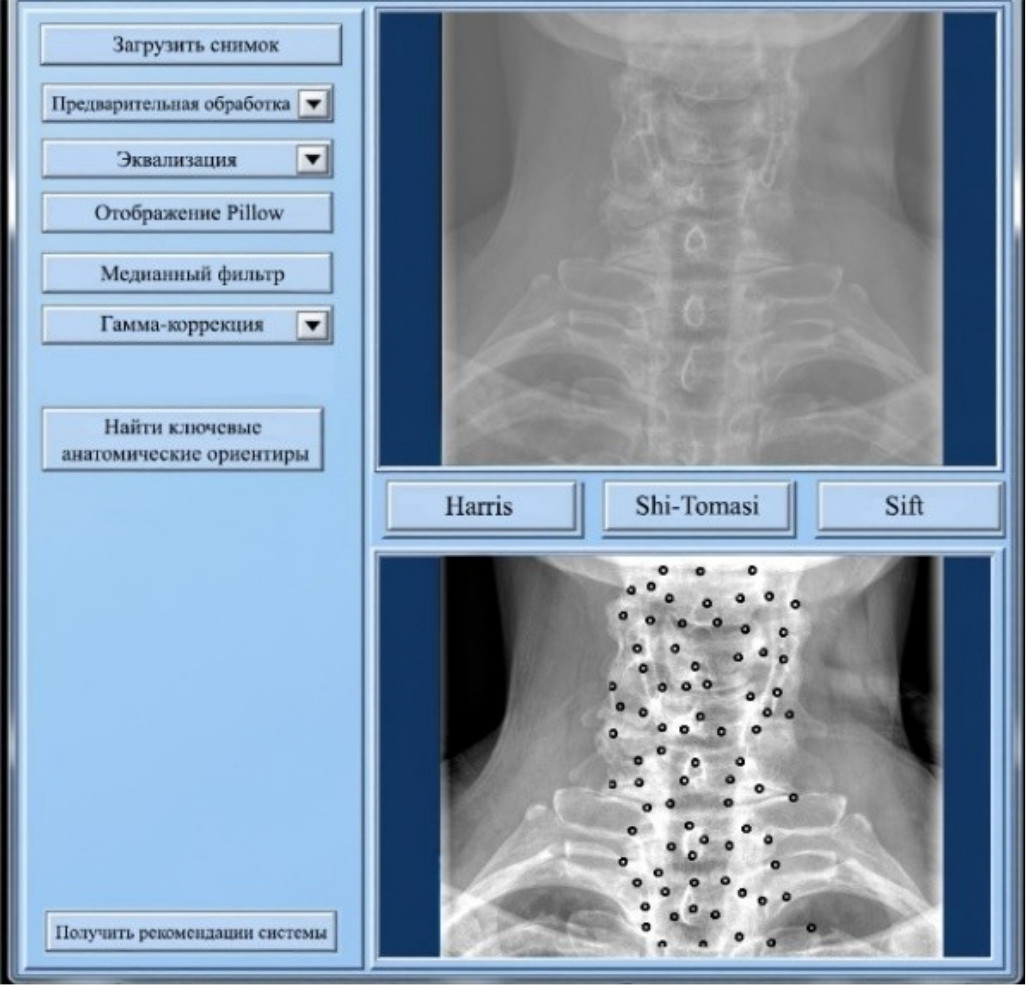

На рис. 9 представлены результаты работы системы поддержки принятия врачебных решений.

Рис. 9. Результаты работы системы поддержки принятия врачебных решений

Система включает в себя следующие ключевые возможности:

- автоматическая предварительная обработка медицинских изображений. Система использует метод стандартной эквализации, который показал наилучшие результаты по точности распознавания анатомических ориентиров;

- кластеризация и распознавание анатомических ориентиров. Алгоритм Shi-Tomasi применяется для выделения ключевых элементов позвоночника на изображениях, сгруппированных в 5–6 кластеров. Точность распознавания достигает 95 %;

- интеллектуальная система поддержки диагностики. На основе выделенных анатомических ориентиров система может предложить врачу предварительные диагнозы, а также рекомендации по дальнейшему обследованию пациента.